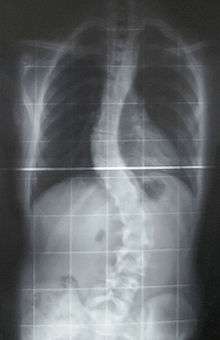

Preoperative (left) and postoperative (right) X-ray of a person with thoracic dextroscoliosis and lumbar levoscoliosis: The X-ray is usually projected such that the right side of the subject is on the right side of the image; i.e., the subject is viewed from the rear (see left image; the right image is seen from the front). This projection is typically used by spine surgeons, as it is how surgeons see their patients when they are on the operating table (in the prone position). This is the opposite of conventional chest X-ray, where the image is projected as if looking at the patient from the front. The surgery was a fusion with instrumentation.